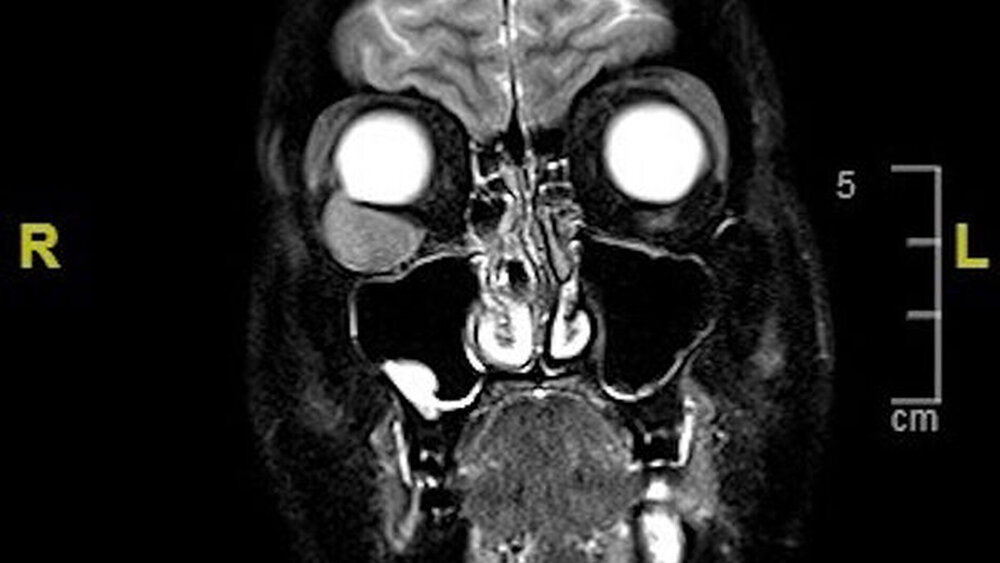

Zur Kontrolle erfolgten MRT-Kontrollaufnahmen des ganzen Körpers in einem dreimonatigen Abstand. Bei Vorstellung in unserer Klinik zeigte sich abgesehen von einem diskreten Bulbushochstand und Exophthalmus rechts ein unauffälliger klinischer Befund. Im MRT zeigte sich eine intraorbitale Raumforderung (Abbildung 1). Die histologische Untersuchung bestätigte den Verdacht auf eine Neumanifestation des Leiomyosarkoms (Abbildungen 2, 3).